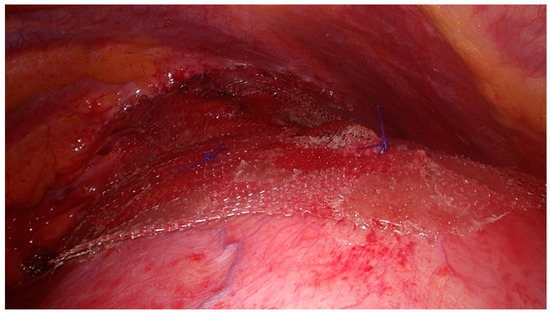

Figure 3.

Diaphragmatic breach, with hernial sac dissected and pushed back in the abdominal cavity.